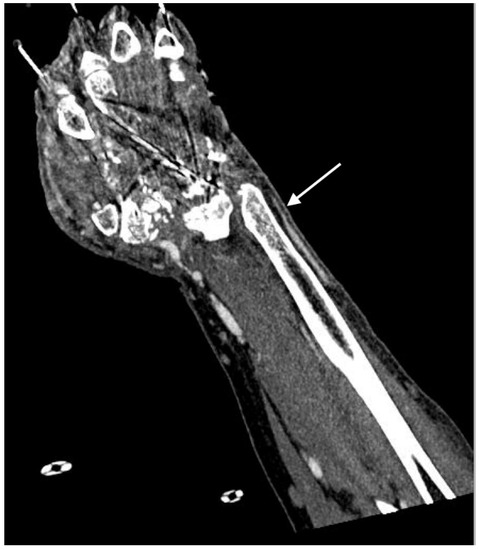

2.4.2. Arterial Occlusion or Stenosis